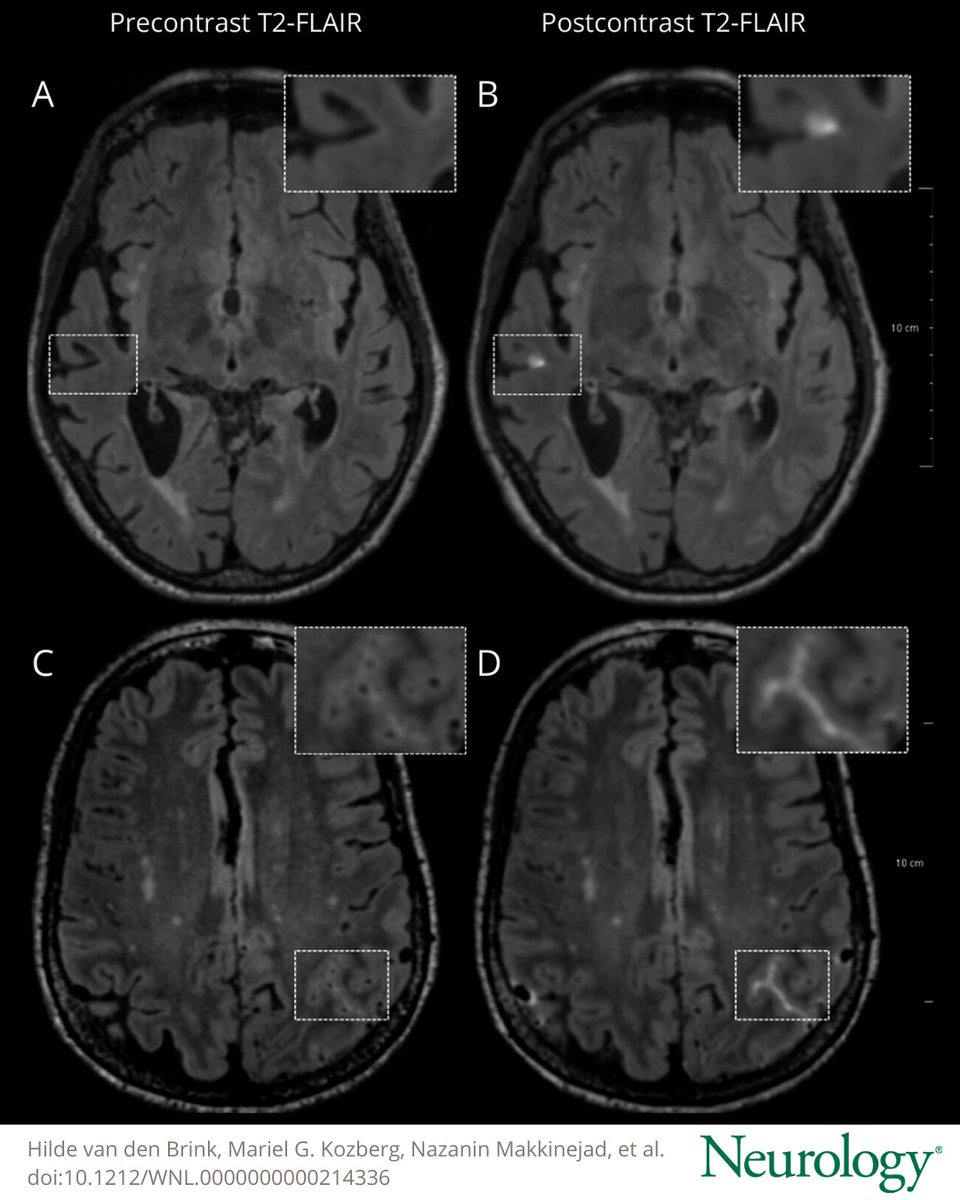

In Vivo Imaging of Blood-Brain Barrier Leakage Using a Contrast Agent in Patients With Cerebral Amyloid Angiopathy https://t.co/PfvVlycJ6m #NeuroTwitter #NeuroX